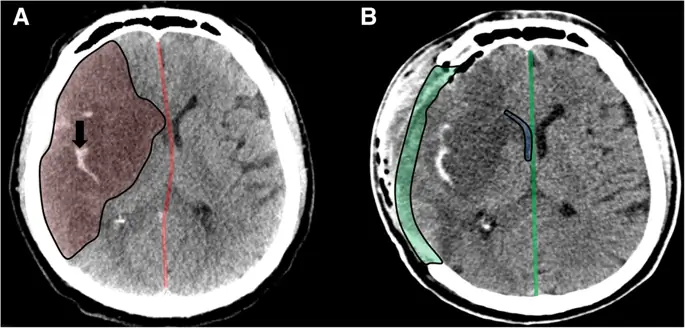

Декомпрессивная гемикраниэктомия при злокачественном ишемическом инсульте. Аксиальная компьютерная томография перед операцией (а), демонстрирующая четко выраженный правосторонний инфаркт MCA (выделено красным) с геморрагическим преобразованием (черная стрелка) и смещением средней линии влево (красная линия). Аксиальная компьютерная томография после операции (b), показывающая дефект краниэктомии (выделено зеленым цветом) с декомпрессированным боковым желудочком (выделено синим цветом) и реверсирование сдвига средней линии (зеленая линия)

Изображение в полном размере

Субокципитальная декомпрессивная краниэктомия при злокачественном инсульте мозжечка. Аксиальная компьютерная томография перед операцией (а), показывающая большой демаркационный инфаркт мозжечка (выделено красным). Осевая КТ после операции (b), демонстрирующая дефект краниэктомии (выделено зеленым) и декомпрессированный четвертый желудочек (выделено синим)